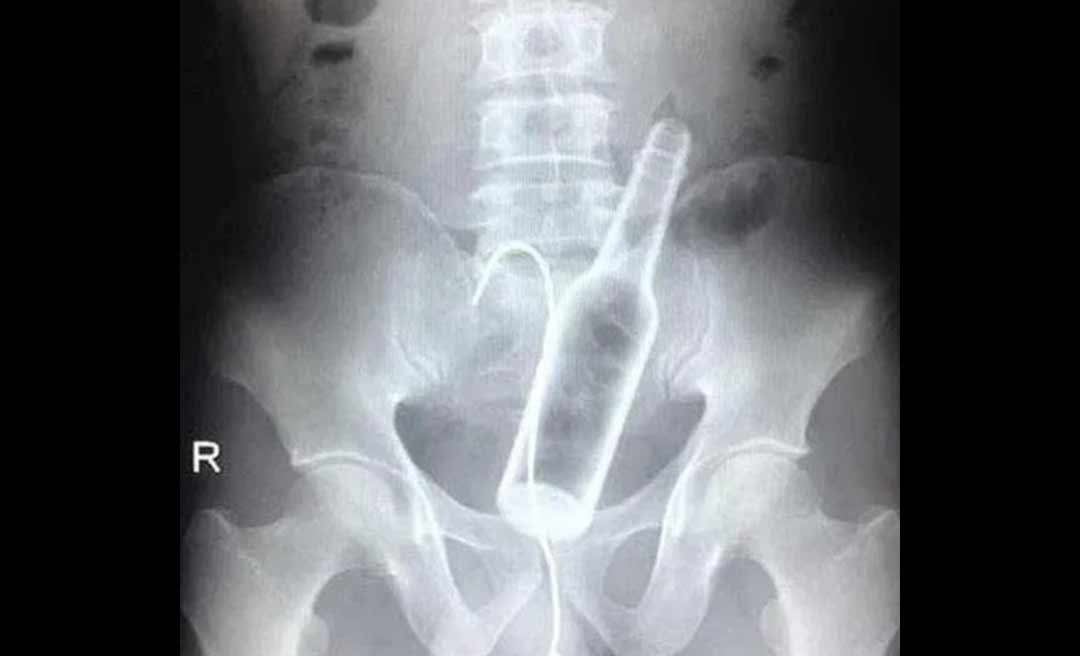

Um jovem de 25 anos, que não teve seu nome revelado, foi transferido no sábado (8) do Hospital Raimundo Chaar, em Brasiléia, no interior do Acre, para o Pronto-socorro de Rio Branco, com uma garrafa de vidro no ânus, segundo o jornal O Alto Acre, informativo eletrônico da fronteira.

Desesperado, o rapaz acionou o Samu. Os socorristas o conduziram ao Hospital Raimundo Chaar, porém os profissionais não conseguiram retirar a garrafa e resolveram tranferi-lo para a capital onde o jovem foi submetido a uma cirurgia para remoção do objeto.